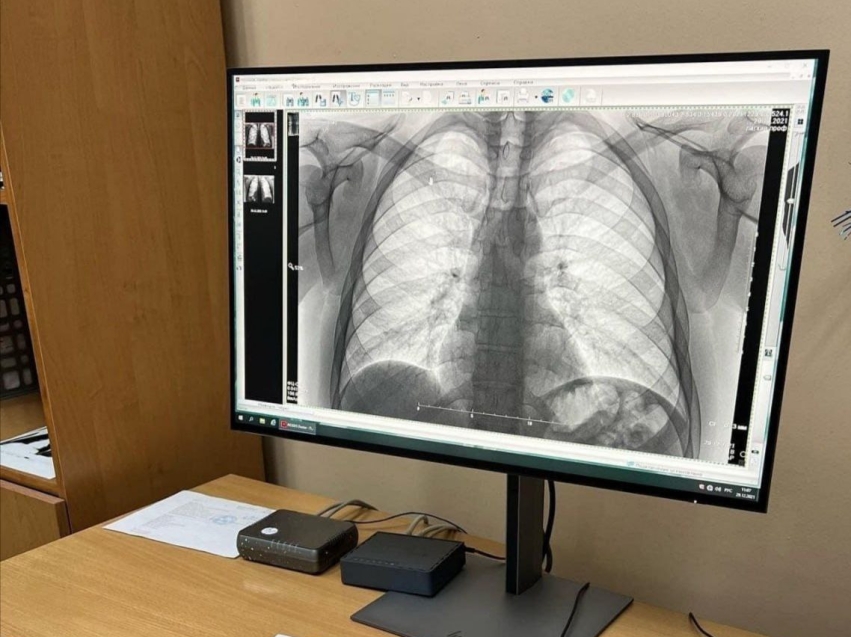

Забайкальцев приглашают пройти обследование на раннее выявление заболеваний легких в преддверии Дня борьбы с туберкулезом

В преддверии Всемирного дня борьбы с туберкулезом в Забайкальском фтизиопульмонологическом центре 22 марта пройдет день открытых дверей. С 10.00 до 12.00 забайкальцы смогут сделать иммунодиагностический тест, а с 10.00 до 16.00 - пройти бесплатный осмотр фтизиатра и флюорографию. С 14.00 до 15.00 на площади имени Ленина состоится ежегодная акция «Белая ромашка» - врачи расскажут про заболевание и методы лечения.

Фото пресс-службы министерства здравоохранения Забайкалья «Врачи центра оценят результаты обследования, дадут рекомендации по ведению здорового образа жизни. При выявлении подозрения на заболевание легких будут проведены дополнительные исследования и назначено лечение. Раннее выявление заболеваний и своевременное начало лечения - это верный шаг к сохранению здоровья», - отметила исполняющая обязанности главного врача учреждения Татьяна Кнестикова.